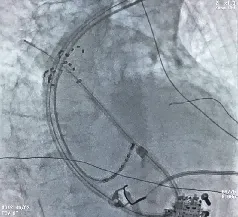

术中造影显示患者下腔静脉极度迂曲,无法经下腔静脉途径送入导管。团队果断改为左腋静脉入路,使用AccuSafe穿刺导丝联合Navigo 8.5Fr可调弯鞘进行房间隔穿刺,并采用本中心首创的Y阀造影剂显影方法确认进入左房。术中借助可调弯鞘灵活适配至上腔静脉入路角度,实现与房间隔稳定贴靠;依托穿刺导丝的滑脱保护及穿刺兼导引的双重安全特性,避免了误穿心包、主动脉及鞘管前冲损伤,在X线引导下精准、安全完成穿间隔操作,充分体现了团队的娴熟技术与应变能力。随后送入Farapulse PFA导管,对双侧肺静脉及上腔静脉进行消融隔离,共放电37次,验证完全阻断,手术获得成功(见图4)。

左1左2为房间隔穿刺过程;右1肺右上肺静脉花瓣状消融;右2:左上肺静脉网篮状消融